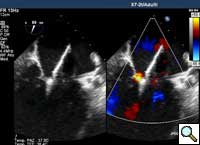

- From the right femoral venous puncture, a TEE guided trans-septal puncture of the septum is performed using a standard transseptal kit (Figure 7) with the Brockenbrough needle, a dilator and a Mullins sheath. The site of the puncture is decided using a standardized approach which optimizes the maneuverability of the delivery system. The puncture is usually high and posterior in the fossa ovalis. After successful septal puncture, the Mullins sheath is parked in the left atrium and the patient is heparinized to achieve an ACT of at least 250 seconds.